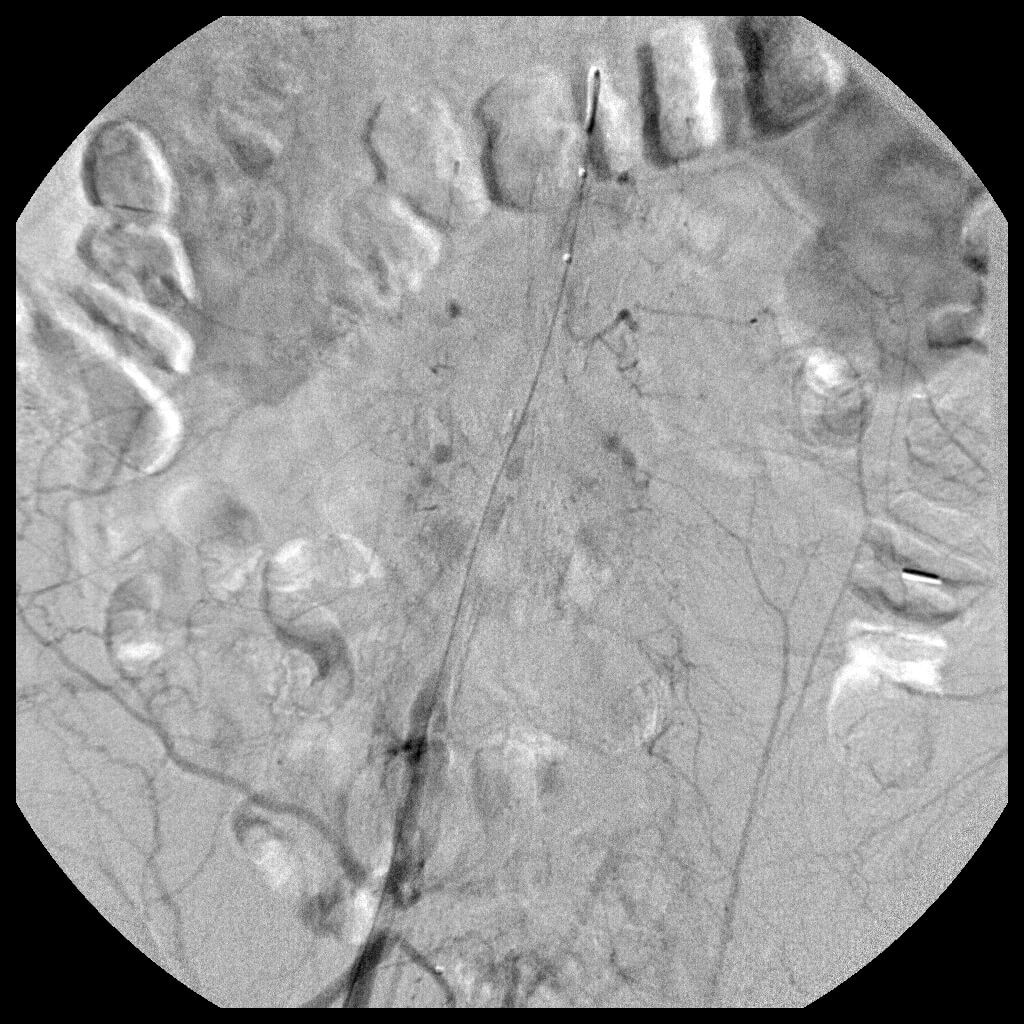

Single image demonstrating post-dilatation of stents placed in the proximal right and left common iliac arteries. -